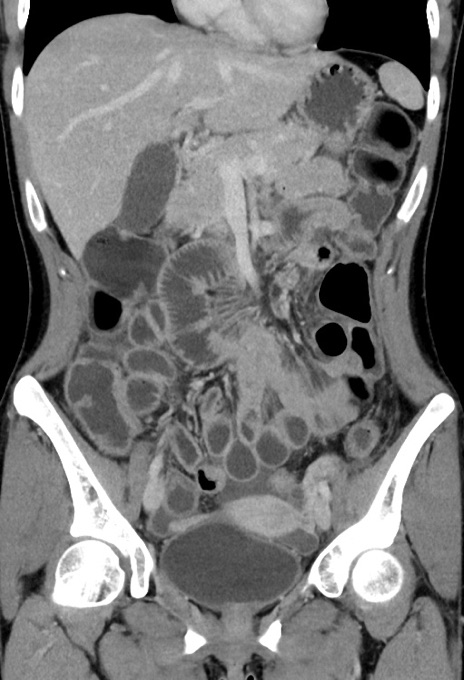

横断像

【症例】20歳代女性

【主訴】嘔吐、下腹部痛

【現病歴】昨日夕食後に嘔吐し下腹部痛が出現。本日になっても嘔吐持続し改善しないため来院。

【身体所見】意識清明、BT 37.2℃、BP 108/67mmHg、腹部:平坦、やや硬、下腹部正中から右にかけて圧痛あり、反跳痛軽度あり、tapping pain(+)。

【データ】WBC 13600、CRP 14.94